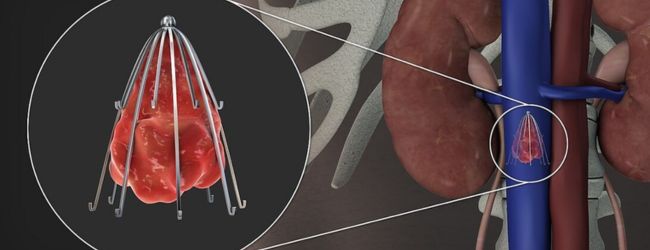

The inferior vena cava (IVC) is the major vein that carries deoxygenated blood from the lower body to the heart. The placement of a filter in this vein is one of the options that can be used as a prophylactic treatment for pulmonary embolism. The filter device is mesh of metallic wires and traps any dislodged clot thereby minimizing the risk of pulmonary embolism. The procedure involves the placement of a filter in IVC through a small incision in the groin or neck with the help of a catheter.